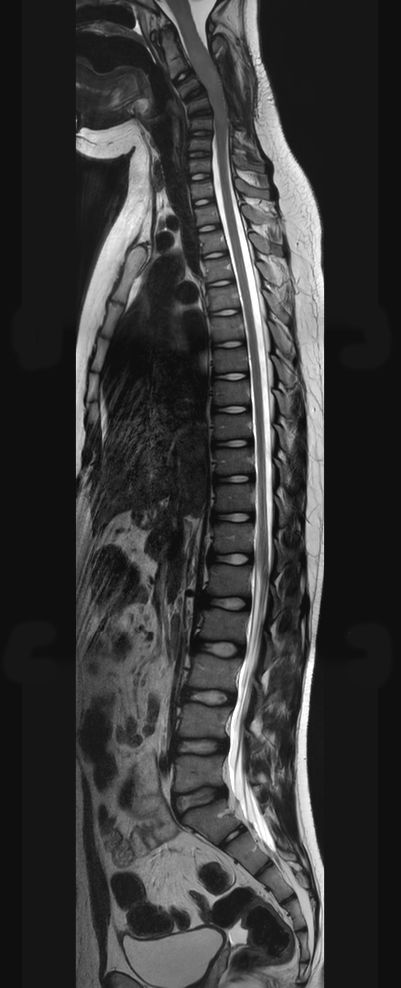

Sagittal T2w TSE (MobiView)